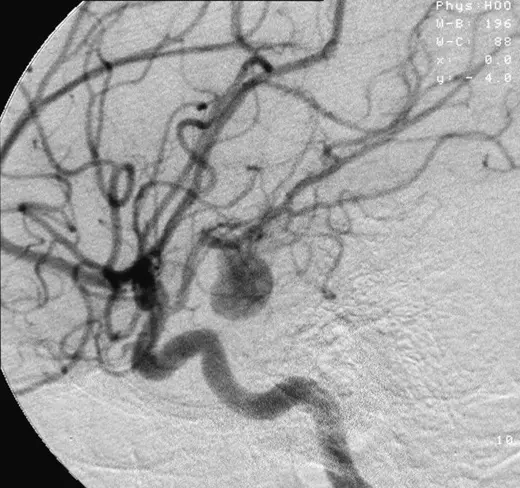

If the result of the CT scan is positive, then the patient should have a cerebral angiogram, which is used to visualise the vessels in the brain and the site of any potential aneurysm.

Image - Angiograph of an aneurysm in a cerebral artery

Creative commons source by Lucien Monfils [CC BY-SA 4.0 (https://creativecommons.org/licenses/by-sa/4.0)]